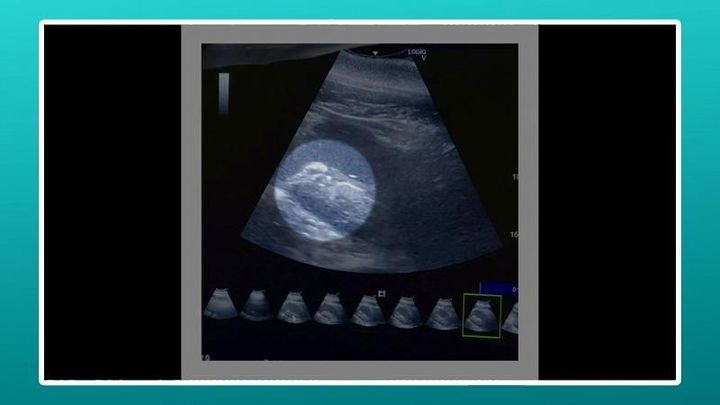

「すご、頭映ってる」「これ確定ですね」

飼育員たちがそう声をあげる先にあるのはエコー検査の画像。

妊娠がわかったのは、バンドウイルカの「メリー」、推定20歳です。

この日、待望の赤ちゃんの姿が確認できたのです。